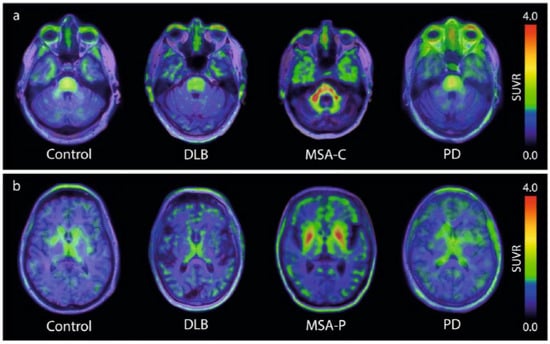

For many years, different laboratories focused on the identification of new hits, with only a few compounds reaching clinical testing stages. A major breakthrough came in 2023, when, for the first time, the tracer [18F]ACI-12589 finally demonstrated that (i) a-synuclein pathology can be visualized by PET and that (ii) the PET signal can differentiate MSA cases from controls and other neurodegenerative cases [9]. As summarized in Figure 1, this brain-penetrating, low molecular weight compound demonstrated high retention in the cerebellar white matter and middle cerebellar peduncles in cases of MSA dominated by cerebellar ataxia (MSA-C). The same result occurred in cases dominated by Parkinsonism (MSA-P), where tracer uptake was also observed in the lentiform nuclei. These observations correlated well with the expected distribution of the a-synuclein pathology in both MSA subtypes, a conclusion based on post-mortem data and clinical presentations [19,20]. With the publication of these first PET images of the a-synuclein pathology in patients diagnosed with MSA, the field finally had a benchmark proving the feasibility of detecting a-synuclein pathology via PET.

Figure 1. [18F]ACI-12589 PET in participants with synucleinopathies. (a) Presentative transversal images from [9] at the level of the middle cerebellar peduncles in a control participant, and patients with DLB, MSA-C and PD. (b) Representative transversal images from [9] at the level of the basal ganglia in a control participant, and patients with DLB, MSA-P and PD. SUVR images for (a,b) are averaged for the 60–90 min time frame and have been created using occipital cortex as a reference region.